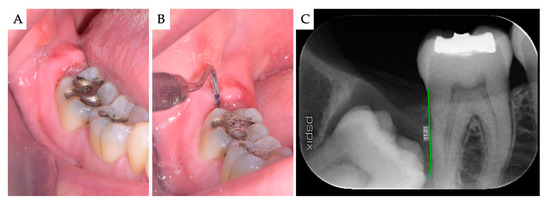

| Case | Gender | Age | Smoker | M3 | Impaction | Follow-Up (years) | PD T0 (mm) | PD T1 (mm) | BD T0 (mm) | BD T1 (mm) | BG (mm) |

|---|---|---|---|---|---|---|---|---|---|---|---|

| 1 | F | 51 | No | 48 | Mesio-angular | 2 | 12 | 3 | 11.1 | 5.2 | 5.86 |

| 2 | F | 36 | No | 38 | Horizontal | 2 | - | 1 | 7.4 | 1.3 | 6.1 |

| 3 | M | 42 | No | 38 | Horizontal | 1 | - | 2 | 10.2 | 4.4 | 5.79 |

| 4 | M | 34 | No | 48 | Horizontal | 1 | - | 2 | 8.6 | 2.1 | 6.51 |

| Mean | 40.75 | 1.5 | 2.00 | 9.33 | 3.25 | 6.07 | |||||

| SD | 6.61 | 0.5 | 0.71 | 1.43 | 1.6 | 0.28 |